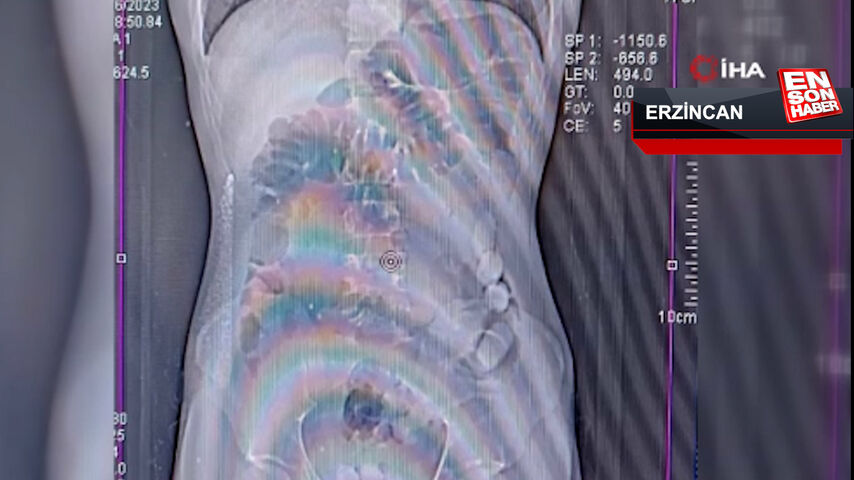

Erzincan’da midede uyuşturucu sevkiyatı

Erzincan polisinin uyuşturucu madde kuryeliği yapan şahıslara yönelik düzenlediği operasyonda, uyuşturucuyu midesine gizleyen İran uyruklu 2 kişi tutuklandı. 1,748 gr Afyon sakızı ele geçirildi.